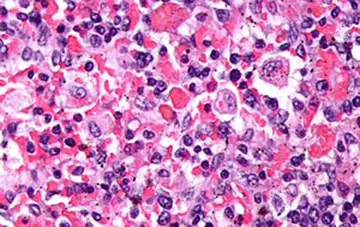

هماتولوژی - صفحه 6